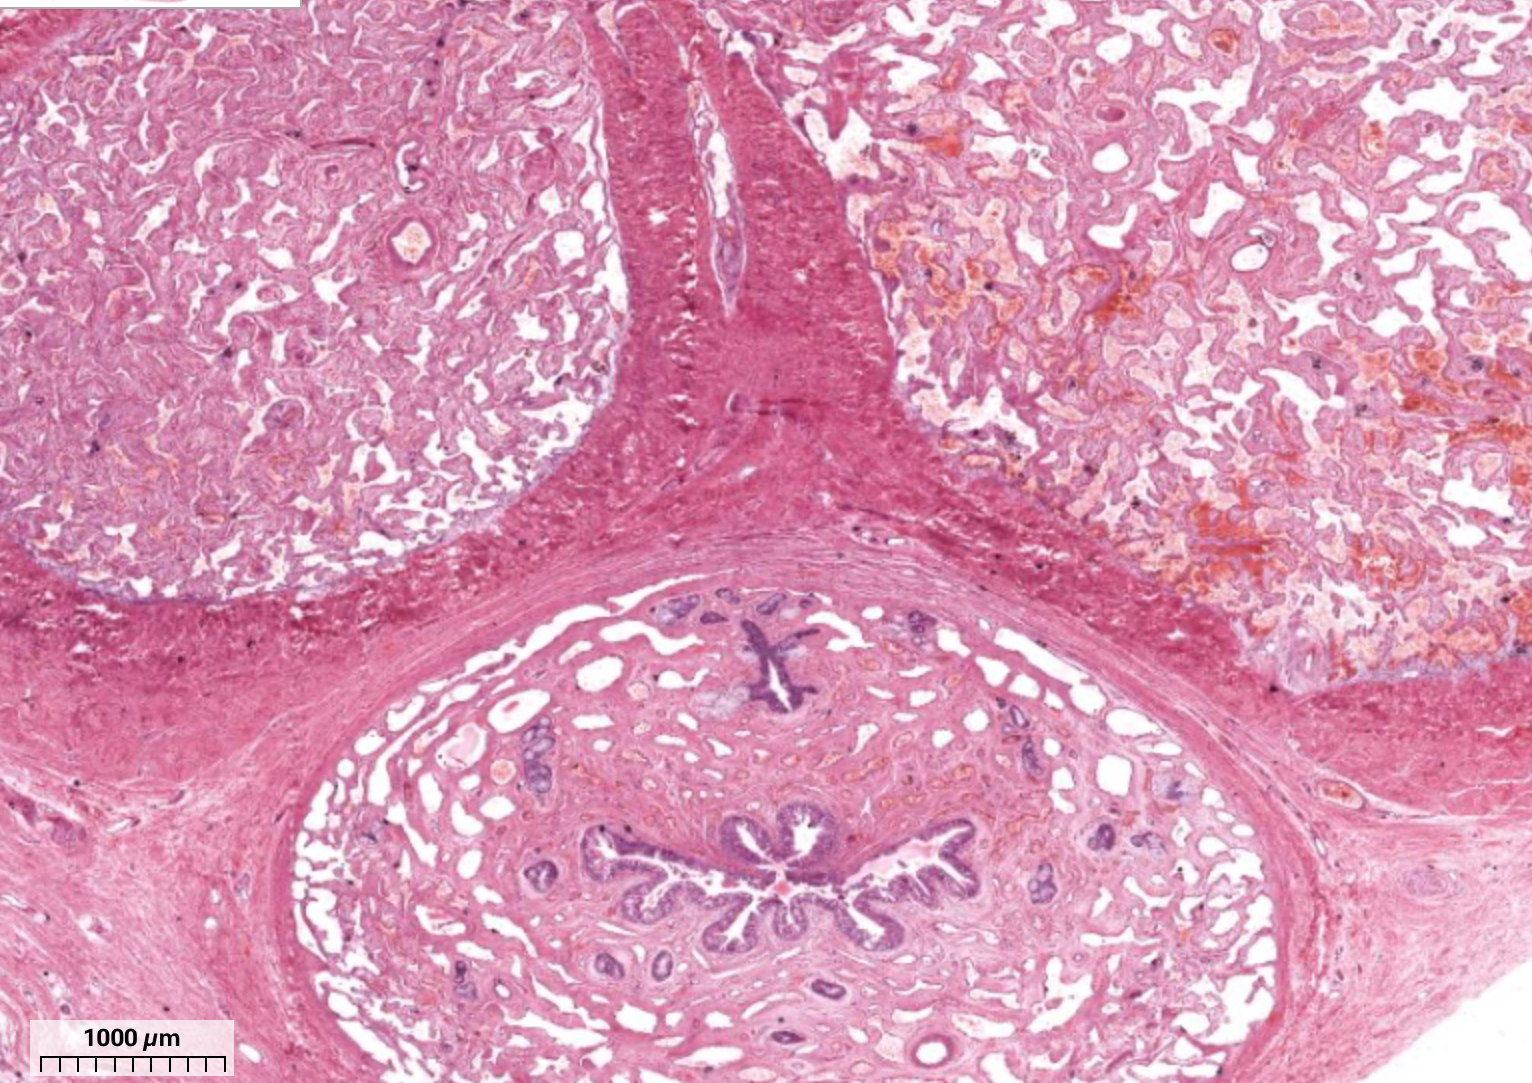

histo; each “circle”

seminiferous tubule

histo; “clumps” between circles

leydig cell